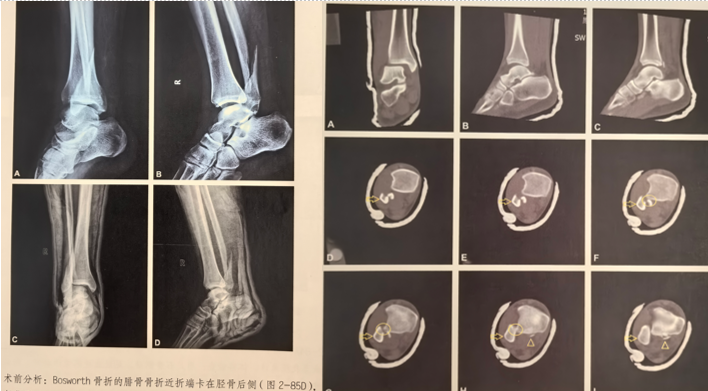

目前我查找相关足踝外科书籍发现关于BF骨折的专门手术研究很少,在《积水潭足踝骨折》一书中发现了一例BF的手术介绍,摘抄如下:

首先通过X线片、CT明确骨折类型及骨折细节,此例腓骨骨折属于WeberB型,通过CT发现内侧间隙增大,考虑三角韧带损伤的可能较大,同时后踝骨折块较小。

作者选择后外侧入路,先复位腓骨,后踝未予处理,未予三角韧带修补,复位腓骨后检查下胫腓间隙不稳定行下胫腓螺钉固定。术后CT可见下胫腓间隙复位可。作者术中通过复位外踝、下胫腓间隙后透视见内踝间隙匹配可。